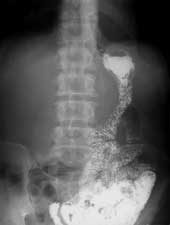

Наиболее обширная операция, выполняемая на желудке, при тотальном или субтотальном опухолевом поражении - это гастрэктомия (Рис. 5). После подобной операции формируется анастомоз между пищеводом и тонкой кишкой с разнообразными типами эзофагоеюностомий. Вначале рентгенологическое исследование выполняется для изучения состояния анастомоза. В первые месяцы после операции наличие отека слизистой и спазма приводят к задержке контрастного вещества выше места анастомоза. Возникает незначительная компенсаторная дилятация дистальных отделов пищевода. Заполняемая отводящая кишка также спазмирована, хотя после стихания реактивного анастомозита она увеличивается в просвете и контрастное вещество свободно поступает в ее дистальный отдел. В последующем наблюдается постепенное расширение проксимальных отрезков кишки с перестройкой рельефа слизистой оболочки по продольному типу. В зависимости от характера выполненной операции, бариевая взвесь может поступать и в приводящую петлю тощей кишки. Рассматривая вопросы моторики подвздошной кишки, большинство исследователей отмечают снижение ее эвакуаторной функции.

Рис. 5. Гастроэктомия с формированием эзофагоэнтероанастомоза.